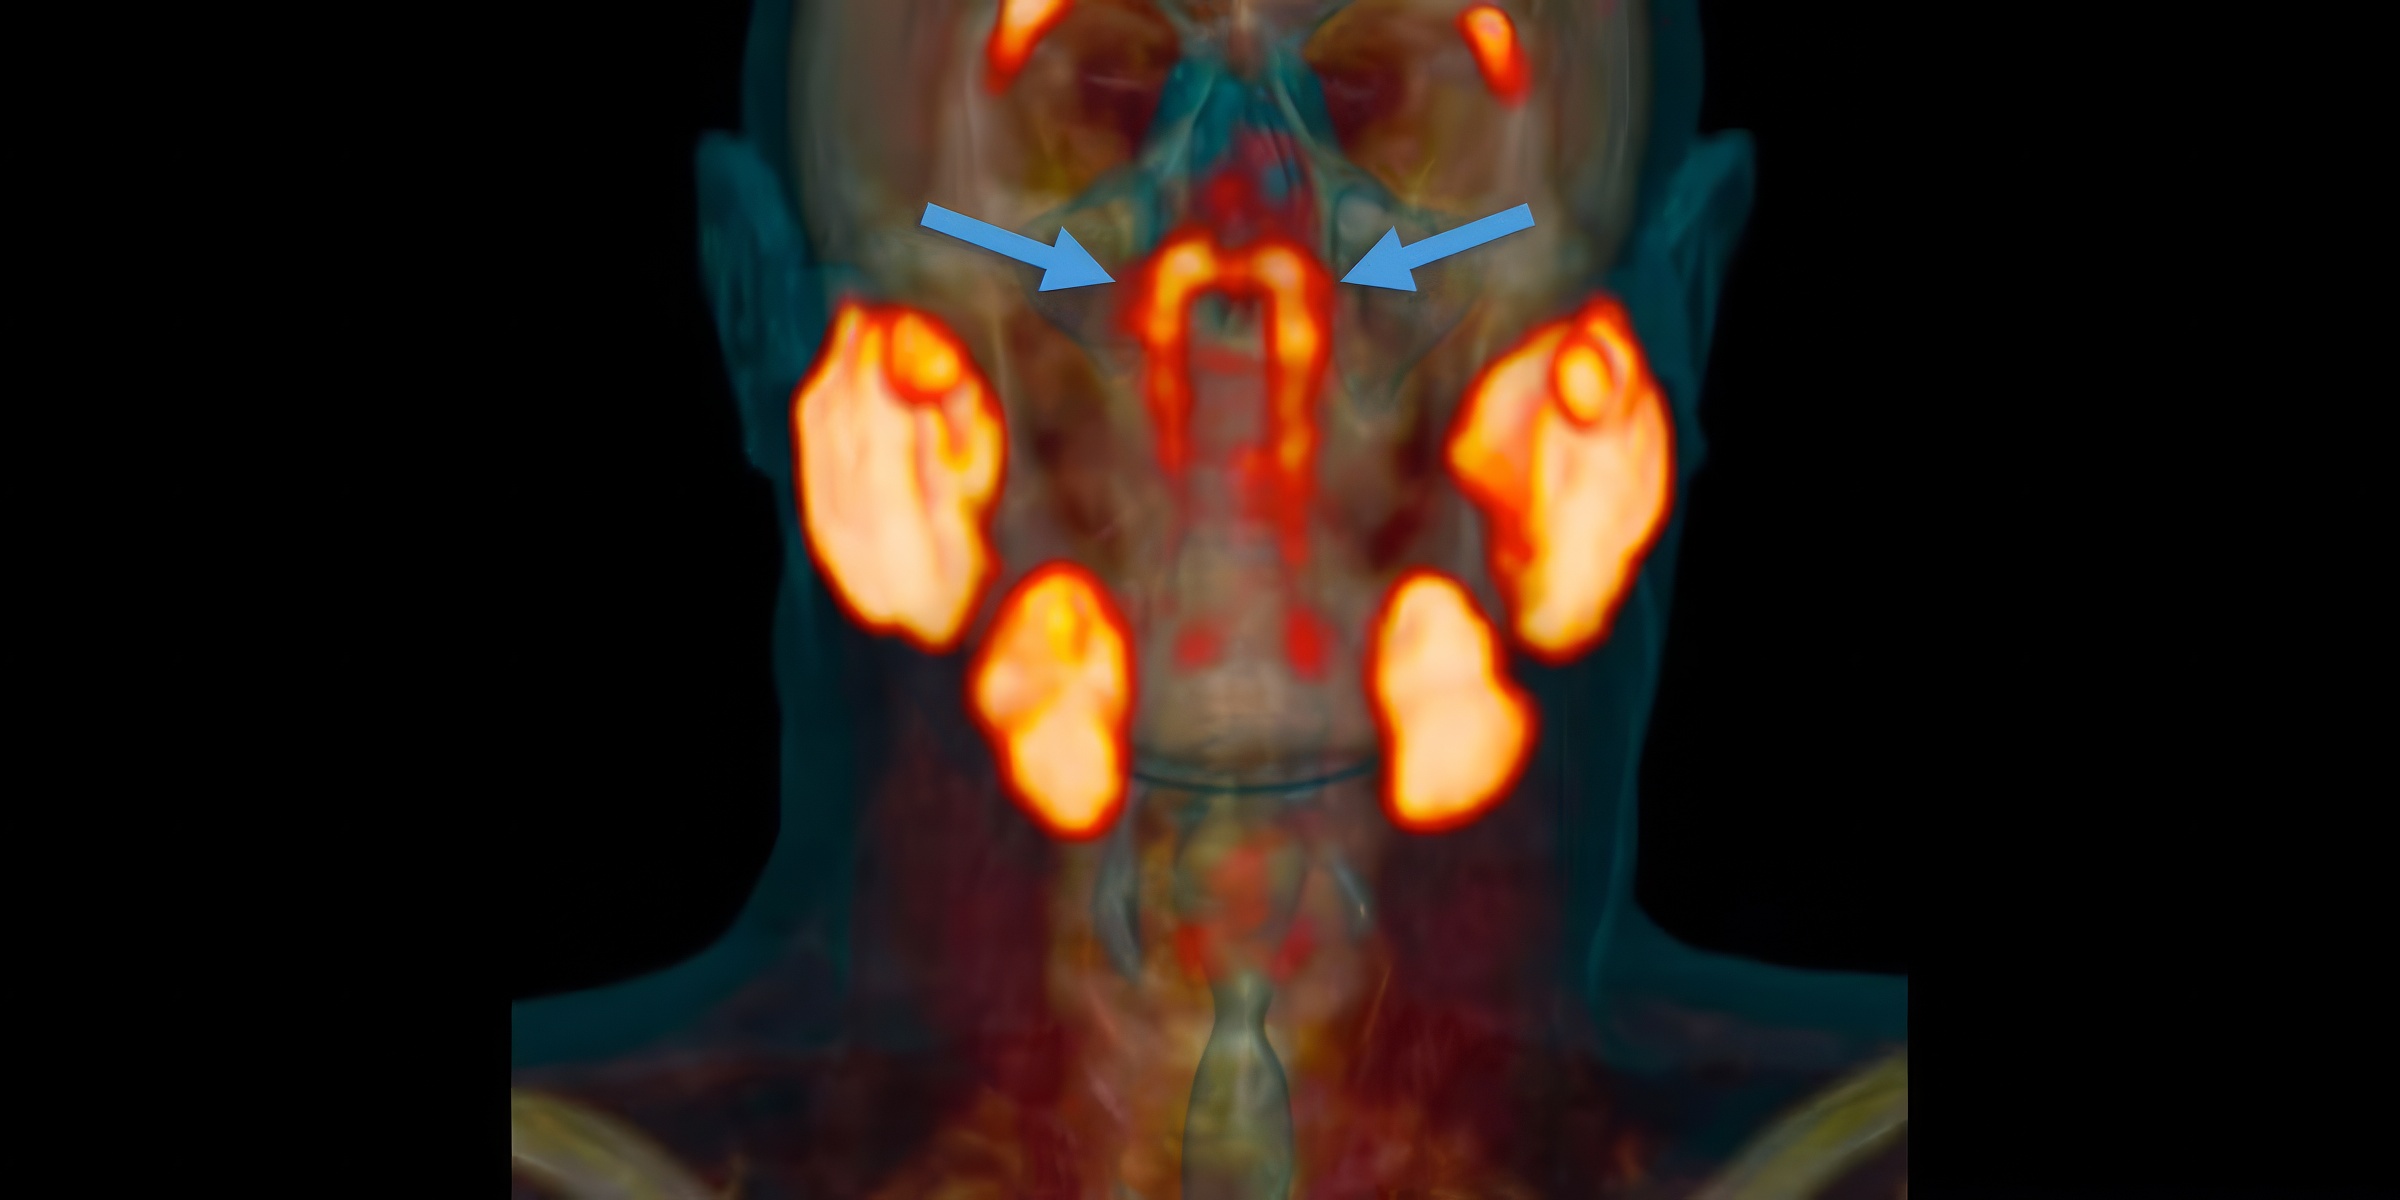

C’est l’une de ces belles histoires de ‘sérendipité’ en science, une découverte faite alors qu’on cherchait tout autre chose. En septembre 2020, des chercheurs de l’Institut du Cancer des Pays-Bas étudiaient le cancer de la prostate. Pour cela, ils utilisaient des scanners très perfectionnés (CT et PET scans) après avoir injecté aux patients un glucose radioactif. L’idée est que les tumeurs, qui consomment beaucoup de sucre, ‘s’allument’ sur les images.

La surprise sur les scanners : deux zones qui brillent de manière inattendue

Mais en regardant les images de tout le corps, les scientifiques ont remarqué quelque chose d’étrange. Dans la tête des patients, deux zones brillaient de manière très intense, alors qu’il n’y avait aucune tumeur à cet endroit. En y regardant de plus près, ils ont compris qu’ils étaient tombés sur quelque chose d’inconnu : une paire de glandes salivaires dont personne ne soupçonnait l’existence.

Il a bien fallu donner un nom à ce nouvel organe. L’équipe a décidé de les appeler les ‘glandes salivaires tubaires‘. Pourquoi ce nom ? Parce qu’elles se trouvent juste derrière le nez, dans l’espace où la cavité nasale rejoint la gorge, près d’une structure appelée le ‘torus tubaire’. Et leur fonction est la même que celle des autres glandes salivaires : produire de la salive pour lubrifier et humidifier la gorge derrière le nez et la bouche.